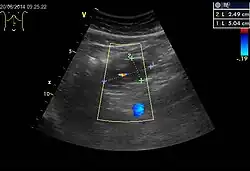

Ultrasonografia endoskopowa (EUS) jest wykorzystywana do oceny miejscowej guza, a podczas biopsji cienkoigłowej pod jej kontrolą pomaga uzyskać reprezentatywny materiał tkankowy[5]. Badanie pomaga określić wielkość guza, jego granice oraz pochodzenie z głębszej warstwy ściany przewodu pokarmowego[12]. Typowo guzy uwidaczniają się jako hipoechogenne zmiany w obrębie mięśniówki właściwej (błona mięśniowa)[45][46][10]. Większe zmiany mogą cechować się nieregularną granicą, obecnością echogennych ognisk oraz torbielowatych przestrzeni[45]. Jednak nie zawsze jest możliwe odróżnienie podczas ultrasonografii endoskopowej GIST od innych guzów mezenchymalnych[10].

W USG nowotwory podścieliskowe przewodu pokarmowego są obrazowane jako hipoechogenne zmiany, które przy odpowiedniej wielkości mogą uciskać sąsiednie struktury anatomiczne[2]. Obecność zmiany w obrębie ściany przewodu pokarmowego znacząco utrudnia jej zobrazowanie, ponadto często występuje znaczna trudność w określeniu lokalizacji zmiany[44].